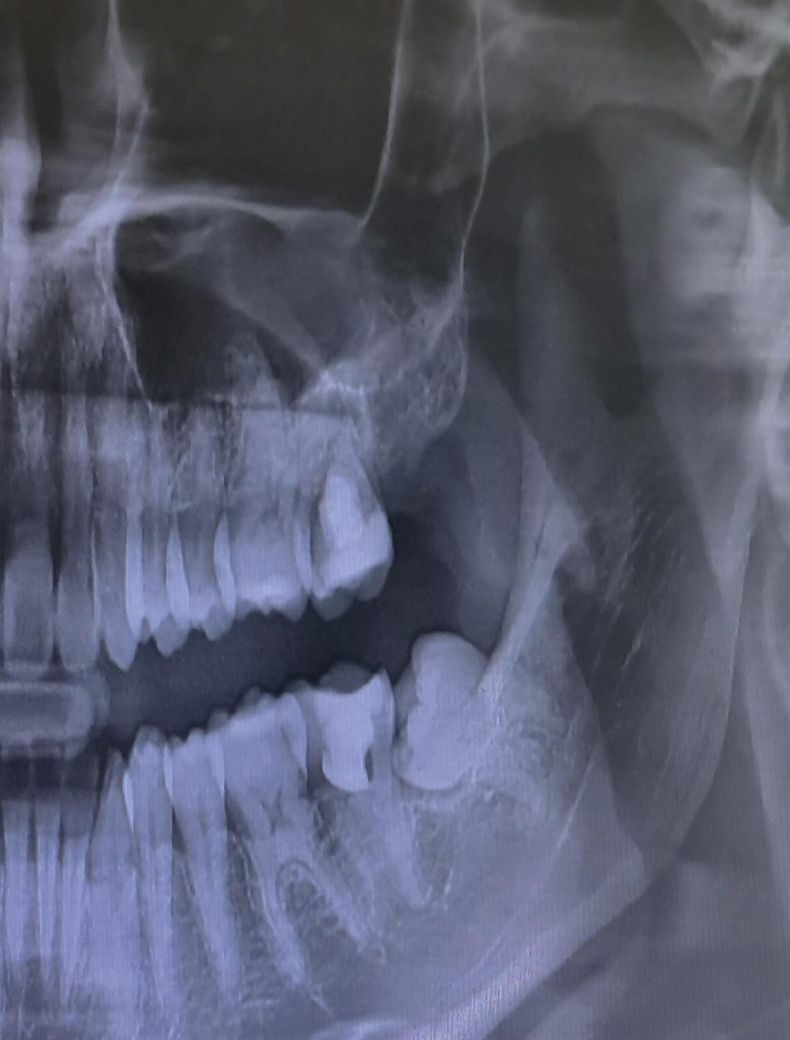

한 곳은 굳이 지금 치료받을 이유없고 전에 신경치료한 부분에 공간이 있어서 통증이 있으면 오라고 하셨는데 어느 진료가 맞는걸까요

• 2번 째 사진

파노라마 사진으로는 치아 사이 충치를 판단하기는 어렵고 작은 사진을 한번 찍어보시는게 좋을것같습니다. 첫번째 사진에서는 인접면 충치가 잇는것처럼 보이긴 합니다.

1. 일단 위, 아래 어금니 둘 다 완전히 신경을 제거한 신경치료를 한 것은 아닙니다. 부분 신경치료를 해둔 것이고 해당 치아는 증상 없으면 굳이 안 건드리는 것이 좋습니다.

2. 아래 신경치료한 어금니 앞의 어금니(제1대구치)는 지금 엑스레이 사진 가지고는 단정지을 순 없지만 충치가 있을 가능성도 있습니다. 평소 사이로 음식물이 많이 끼거나 시리거나 했다면 충치일 확률이 높습니다